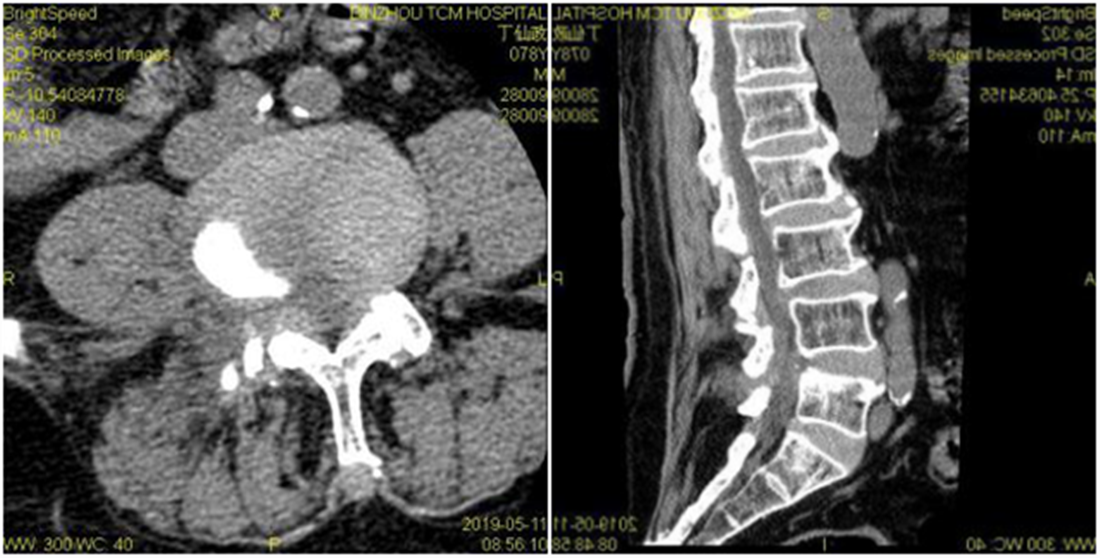

入院后经过详尽询问病史、仔细查体及全面影像检查及分析。患者存在腰部脊椎的纵向的失稳,在站立时存在椎间隙变窄,椎间盘组织进一步突出明显。针对此病患的传统理念,是行腰椎椎弓根螺钉固定加以椎间隙植骨融合术治疗,但由于该患者年龄较大,若以传统理念进行手术,对此高龄患者的创伤较大,恢复期较长。综合考虑后,决定为该患者采取椎板开窗髓核摘除术加以棘突间动态固定(COFLEX)术。

术前CT